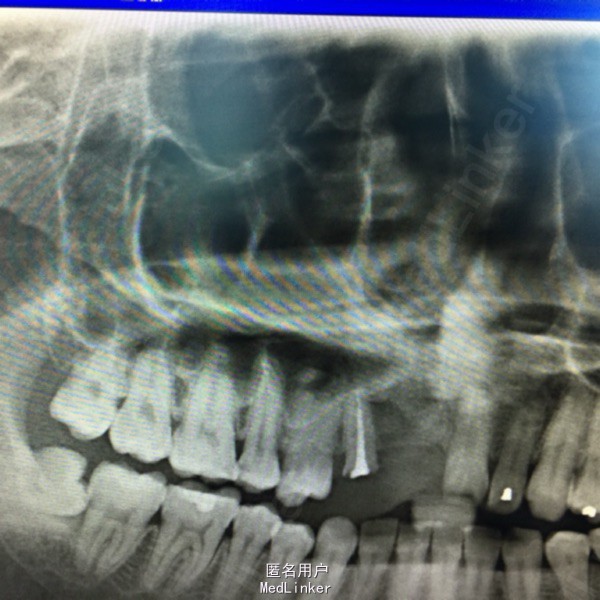

上前牙烤瓷冠修复,13牙冠缺损,叩(+),行桩冠修复。曲面断层片示:13、14根尖可见4x2cm阴影,边缘可见白色阻射线。

诊断:13、14根尖囊肿 处理:1、拆除桩冠。 2、13行牙髓治疗。 3、囊肿行开窗引流术。

患者每天以生理盐水冲洗,2一4次/天,半年复查X片。 该患者1年半后,可见囊腔缩小,新骨长入。无需行囊肿挖除术。